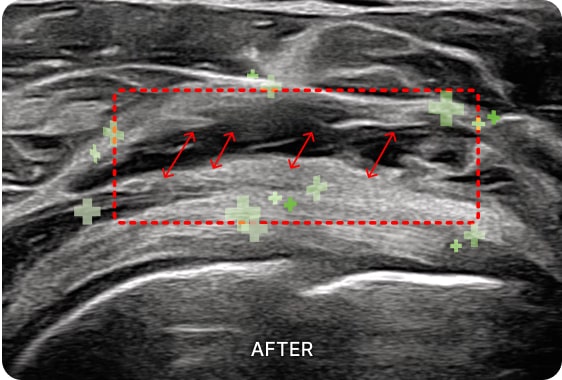

초음파 검사를 통해

회전근개 건염 통증의 직접적인

원인을 확인할 수 있습니다.

회전근개 힘줄의 염증과 두께, 파열, 석회화 정도를

정확하게 파악한 이후 치료 솔루션을 제시합니다.

01. PDRN 약침

PDRN 약침은 인체의 DNA와 90% 이상 유사한 구조로 세포 증식을 활성화하여

손상된 조직을 복구하는 효과가 뛰어납니다. 초음파를 활용하여 신경을 압박하는

염증을 박리하고 손상된 조직을 재생합니다.